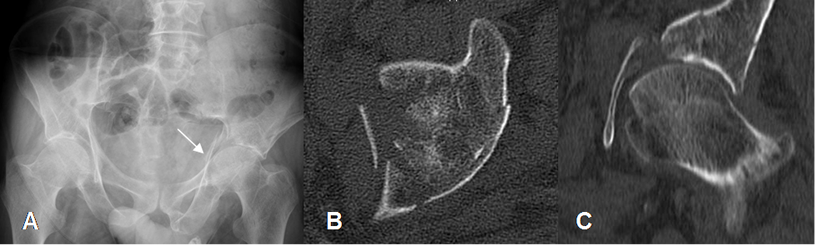

Fig 43. Trauma de pelvis. Compresión vertical.

A: Rx AP. Irregularidad y pérdida de la nitidez de la línea ilioisquial, por fractura.

B: TAC axial y C: TAC reconstrucción sagital. Fractura conminuta e impactada del techo acetabular.

Fig 44. Trauma de pelvis. Compresión vertical.

A: Rx AP. Fractura del reborde interno y superior del acetábulo, que se extiende al hueso iliaco.

B: TAC axial. Fractura acetabular del reborde medial y posterior.

C: TAC reconstrucción 3D, donde se confirman los hallazgos.